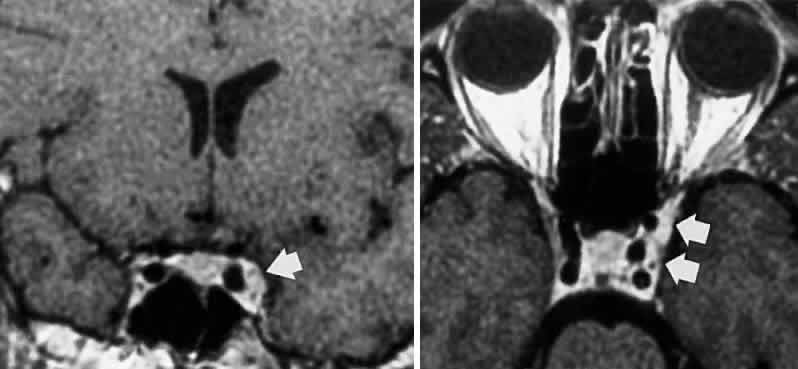

In the cavernous sinus, the abducens nerve may be involved in combination with the ophthalmic-trigeminal, third, or fourth nerves. Abducens monoparesis is frequent with cavernous sinus lesions, perhaps related to the nerve's location within the sinus, inferolateral to the carotid artery and unsupported by the dural wall of the sinus.19,20 Isolated abducens palsy occurs with carotid-cavernous fistulas (especially with spontaneous dural shunts21) and intracavernous aneurysms20 (Fig. 7), and is the earliest indication of contralateral spread of cavernous sinus thrombosis. Sixth nerve palsy accompanied only by ipsilateral Horner's syndrome also points to the cavernous sinus, since the ocular sympathetics from the carotid plexus may be simultaneously involved.22

Fig. 7. A. Chronic isolated sixth nerve palsy. B. Coronal and Axial (C) MRI sections showing large intracavernous internal carotid aneurysm (arrows).